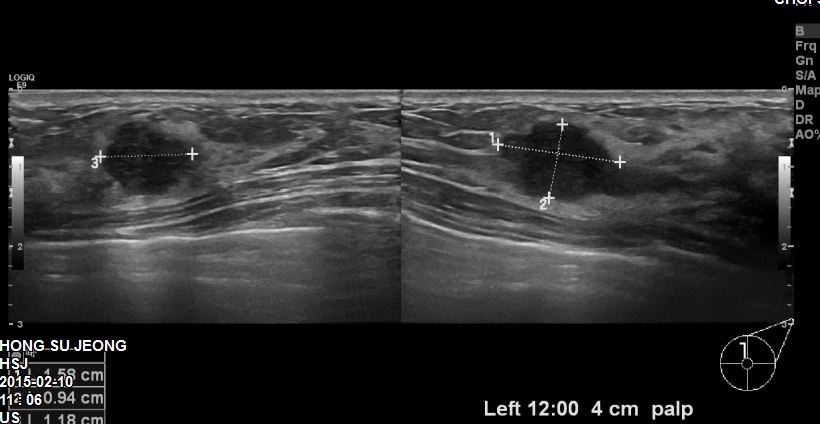

본원에 내원하신 20대 환자분이십니다.

유방초음파 후 좌측유방에 1.58cm의 혹 조직검사시행하였고

침윤성유방암 진단되었습니다.